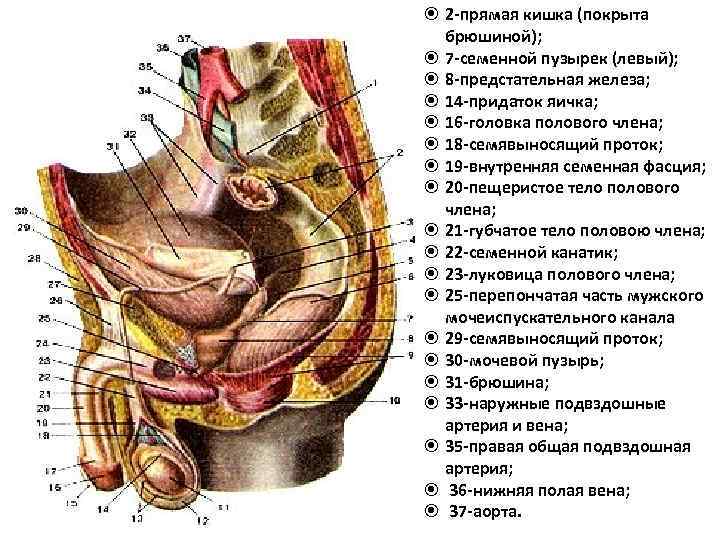

Анатомия малого таза: детальные схемы и изображения